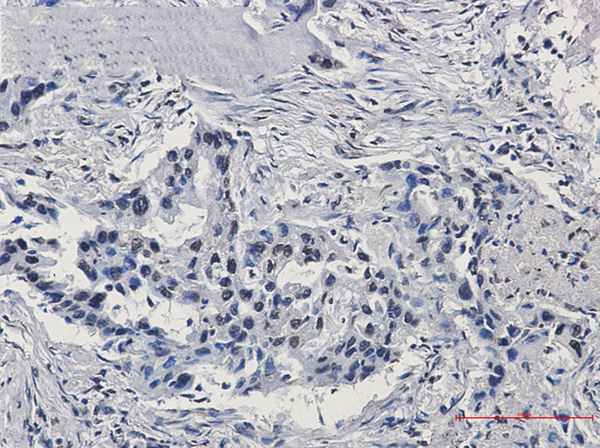

(Detection of human HIF1-alpha by immunohistochemistry. Sample: FFPE section of renal cell carcinoma. Antibody: Affinity purified rabbit anti-HIF1-alpha antibody (AAA214035-3) used at a dilution of 1:100. Detection: DAB)